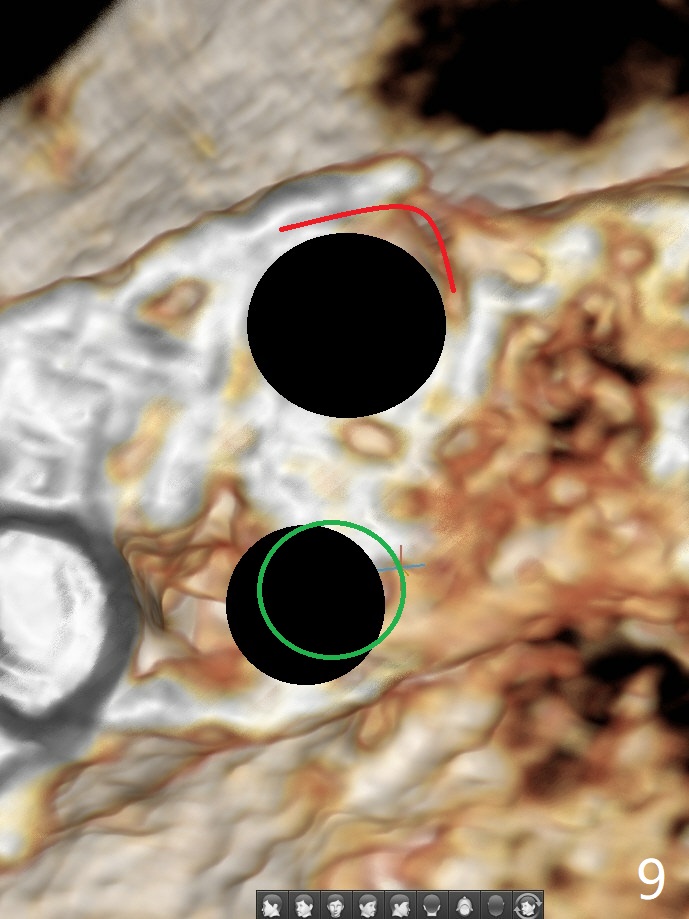

52岁女左上4颊侧牙龈显著肿胀(图一:*(颊侧骨板缺失))伴有瘘道(<),拔除前,在3植牙牙冠切缘舌侧形成开口(图二:*,准备纠正基台不全就位(<);4初步钻洞不正。改变钻头方向后(图三),完成植体放置(图四),并且安置修复基台(4.5x4(2))。磨去3牙冠近中面(图六:*),牙冠和基台反时针旋转(图六:弯箭头),基台完全就位(图四:箭头),调𬌗后,制作4临时牙冠(图六),放置后者前,覆盖半张PRF膜(促进下面粘性骨粉愈合)。图五,六颊侧隆起是因为下面放置许多粘性骨粉。图七是术前CT3D图像(冠状切面),显示颊侧(B),腭侧(P)牙根。拔牙后显示中隔(图八:S),植体植入腭侧窝(图九:绿色),四面骨质包绕,包括中隔;为了修复颊侧骨板,首先放置半张PRF膜(红色)紧贴颊侧骨板腭侧/牙龈,防止骨粉从瘘道流失,然后放置粘性骨粉(图十:粉红色)。术后2.5月3颊侧牙龈仍然红肿(图十一,十二:*),可能与基台袖太短有关(2毫米,图二至四),所以更换袖3毫米的基台(图十三)。术后四个月(牙冠粘固)3颊侧牙龈炎症明显减退(资料没有显示)。术后2.5月4颊侧骨板没有塌陷(图十二,与术后即刻对比(图六))。3基台放置太颊侧,所以在牙冠腭侧制作小的开口(图十四:>),让多余粘固剂流出。取模前3螺丝就拧紧(35Ncm),而4由于有大的开口,粘固后才拧紧(30Ncm)。两个邻牙其中一个可以取出,容易去除另外一个牙冠残余粘固剂。